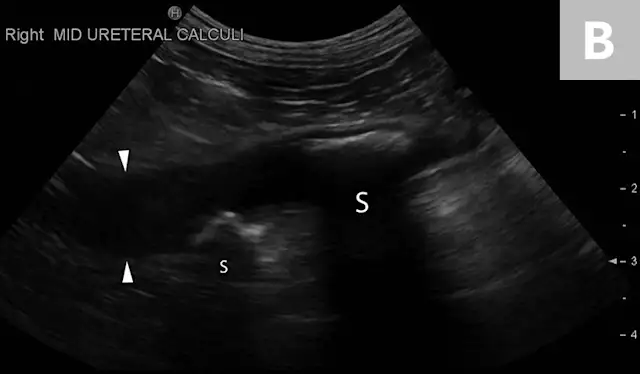

Clinical signs associated with ureteral calculi may range from chronic non-specific signs to acute or chronic renal failure. The presence of hydronephrosis can be highly suggestive of a ureteral obstruction (Figure 6).

FIGURE 6A

Mild to moderate right hydronephrosis and proximal ureteral dilation in a Dalmatian.